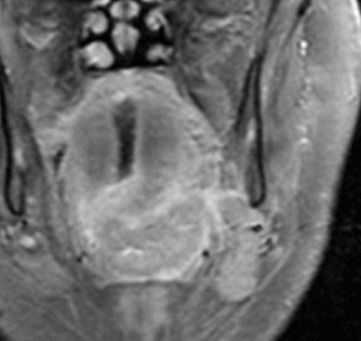

(Слева) При МРТ Т2ВИ FS в аксиальной проекции у пациента 50 лет с объемным образованием левой небной миндалины визуализируется экзофитная опухоль В неоднородной структуры. Ровный боковой край опухоли означает отсутствие глубокой инвазии.

(Справа) При МРТ Т1 DB С+ FS в корональной проекции у этого же пациента визуализируется крупная опухоль (плоскоклеточный рак) левой небной миндалины, экзофитного характера, имеющая ножку. МРТ позволяет отчетливо продемонстрировать отсутствие глубокого распространения опухоли в медиальную крыловидную мышцу. Стадия опухоли соответствует T3N0M0 (третья стадия заболевания), пациенту была назначена химиотерапия.